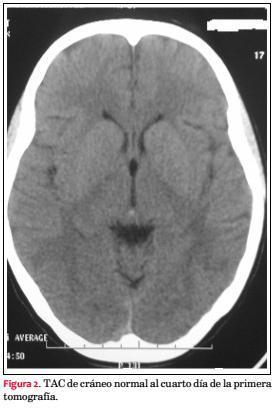

Un día después se registran cifras elevadas de PA, hasta 150/100 mmHg. Se inicia tratamiento con alfa-metildopa 500 mg cada 8 horas, y amlodipina 5 mg cada 12 horas, estabilizándose la PA en 120/90 mmHg. Al día siguiente instala cefaleas, con PA 130/90 mmHg y reitera convulsión tónico-clónica generalizada, debiendo recibir diazepam intravenoso para yugular la crisis. Se reinstala carga e infusión continua de sulfato de Mg. Evoluciona con cefaleas, amaurosis, parestesias y paresia de miembro superior izquierdo (MSI). Se realiza TAC de cráneo que evidencia área hipodensa córtico subcortical occipital, compatible con SLEPR (figura 1), y en el mismo acto angio-TAC, no observándose trombosis de senos venosos. El electroencefalograma (EEG) mostró sufrimiento encefálico difuso, con actividad paroxística focal derecha, en regiones central y temporal. Se continuó con la medicación antihipertensiva, manteniendo valores de PA sistólica de 90-100 mmHg, cediendo la cefalea, y retrocediendo toda la sintomatología neurológica.

Las manifestaciones neurológicas, amaurosis bilateral, parestesias y paresia de MSI permitieron hacer el diagnóstico clínico de SLEPR, que se confirmó con la TAC de cráneo por la presencia de áreas hipodensas corticales occipitales que revirtieron completamente en el control posterior. Estas imágenes evidenciaron edema cerebral vasogénico. El diagnóstico de SLEPR es clínico-radiológico (resonancia magnética/tomografía computada), obteniéndose imágenes de edema vasogénico simétrico bilateral en territorio de la circulación cerebral posterior con distribución preferente en la sustancia blanca subcortical y frecuente en lóbulo parietal y occipital en 98% de los casos(12). El edema cerebral se explica por mecanismos patogénicos no excluyentes, la encefalopatía hipertensiva y la disfunción endotelial. Se observa en diferentes situaciones clínicas, siendo el precipitante común un aumento brusco de la PA(13). Existen condiciones asociadas a SLEPR, como sepsis, enfermedades autoinmunes (lupus eritematoso sistémico), o síndrome antifosfolipídico, que fueron descartadas en esta paciente.